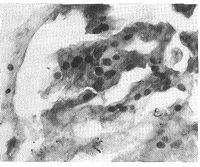

11例鳞癌、6例腺癌和2例腺鳞癌芳香化酶mRNA表达均为阳性,3例小细胞肺癌和1例肺泡细胞癌均为弱阳性。阳性信号主要分布于癌细胞的胞浆和胞核内(图1、2),肿瘤的间质细胞和血管内皮细胞也有少量表达(图3)。而作为对照的癌旁组织、肺良性疾病及其相应的正常肺组织均为阴性(图4)。

图1 肺腺癌芳香化酶mRNA阳性表达细胞(原位杂交×200)

Fig 1 Positive stained cells of aromatase mRNA in adenocarcinoma (in situ hybridizition, ISH×200)

图2 肺鳞癌芳香化酶mRNA阳性表达细胞(原位杂交×200)

Fig 2 Positive stained cells of aromatase mRNA in squamous cell carcinoma (in situ hybridization, ISH×200)